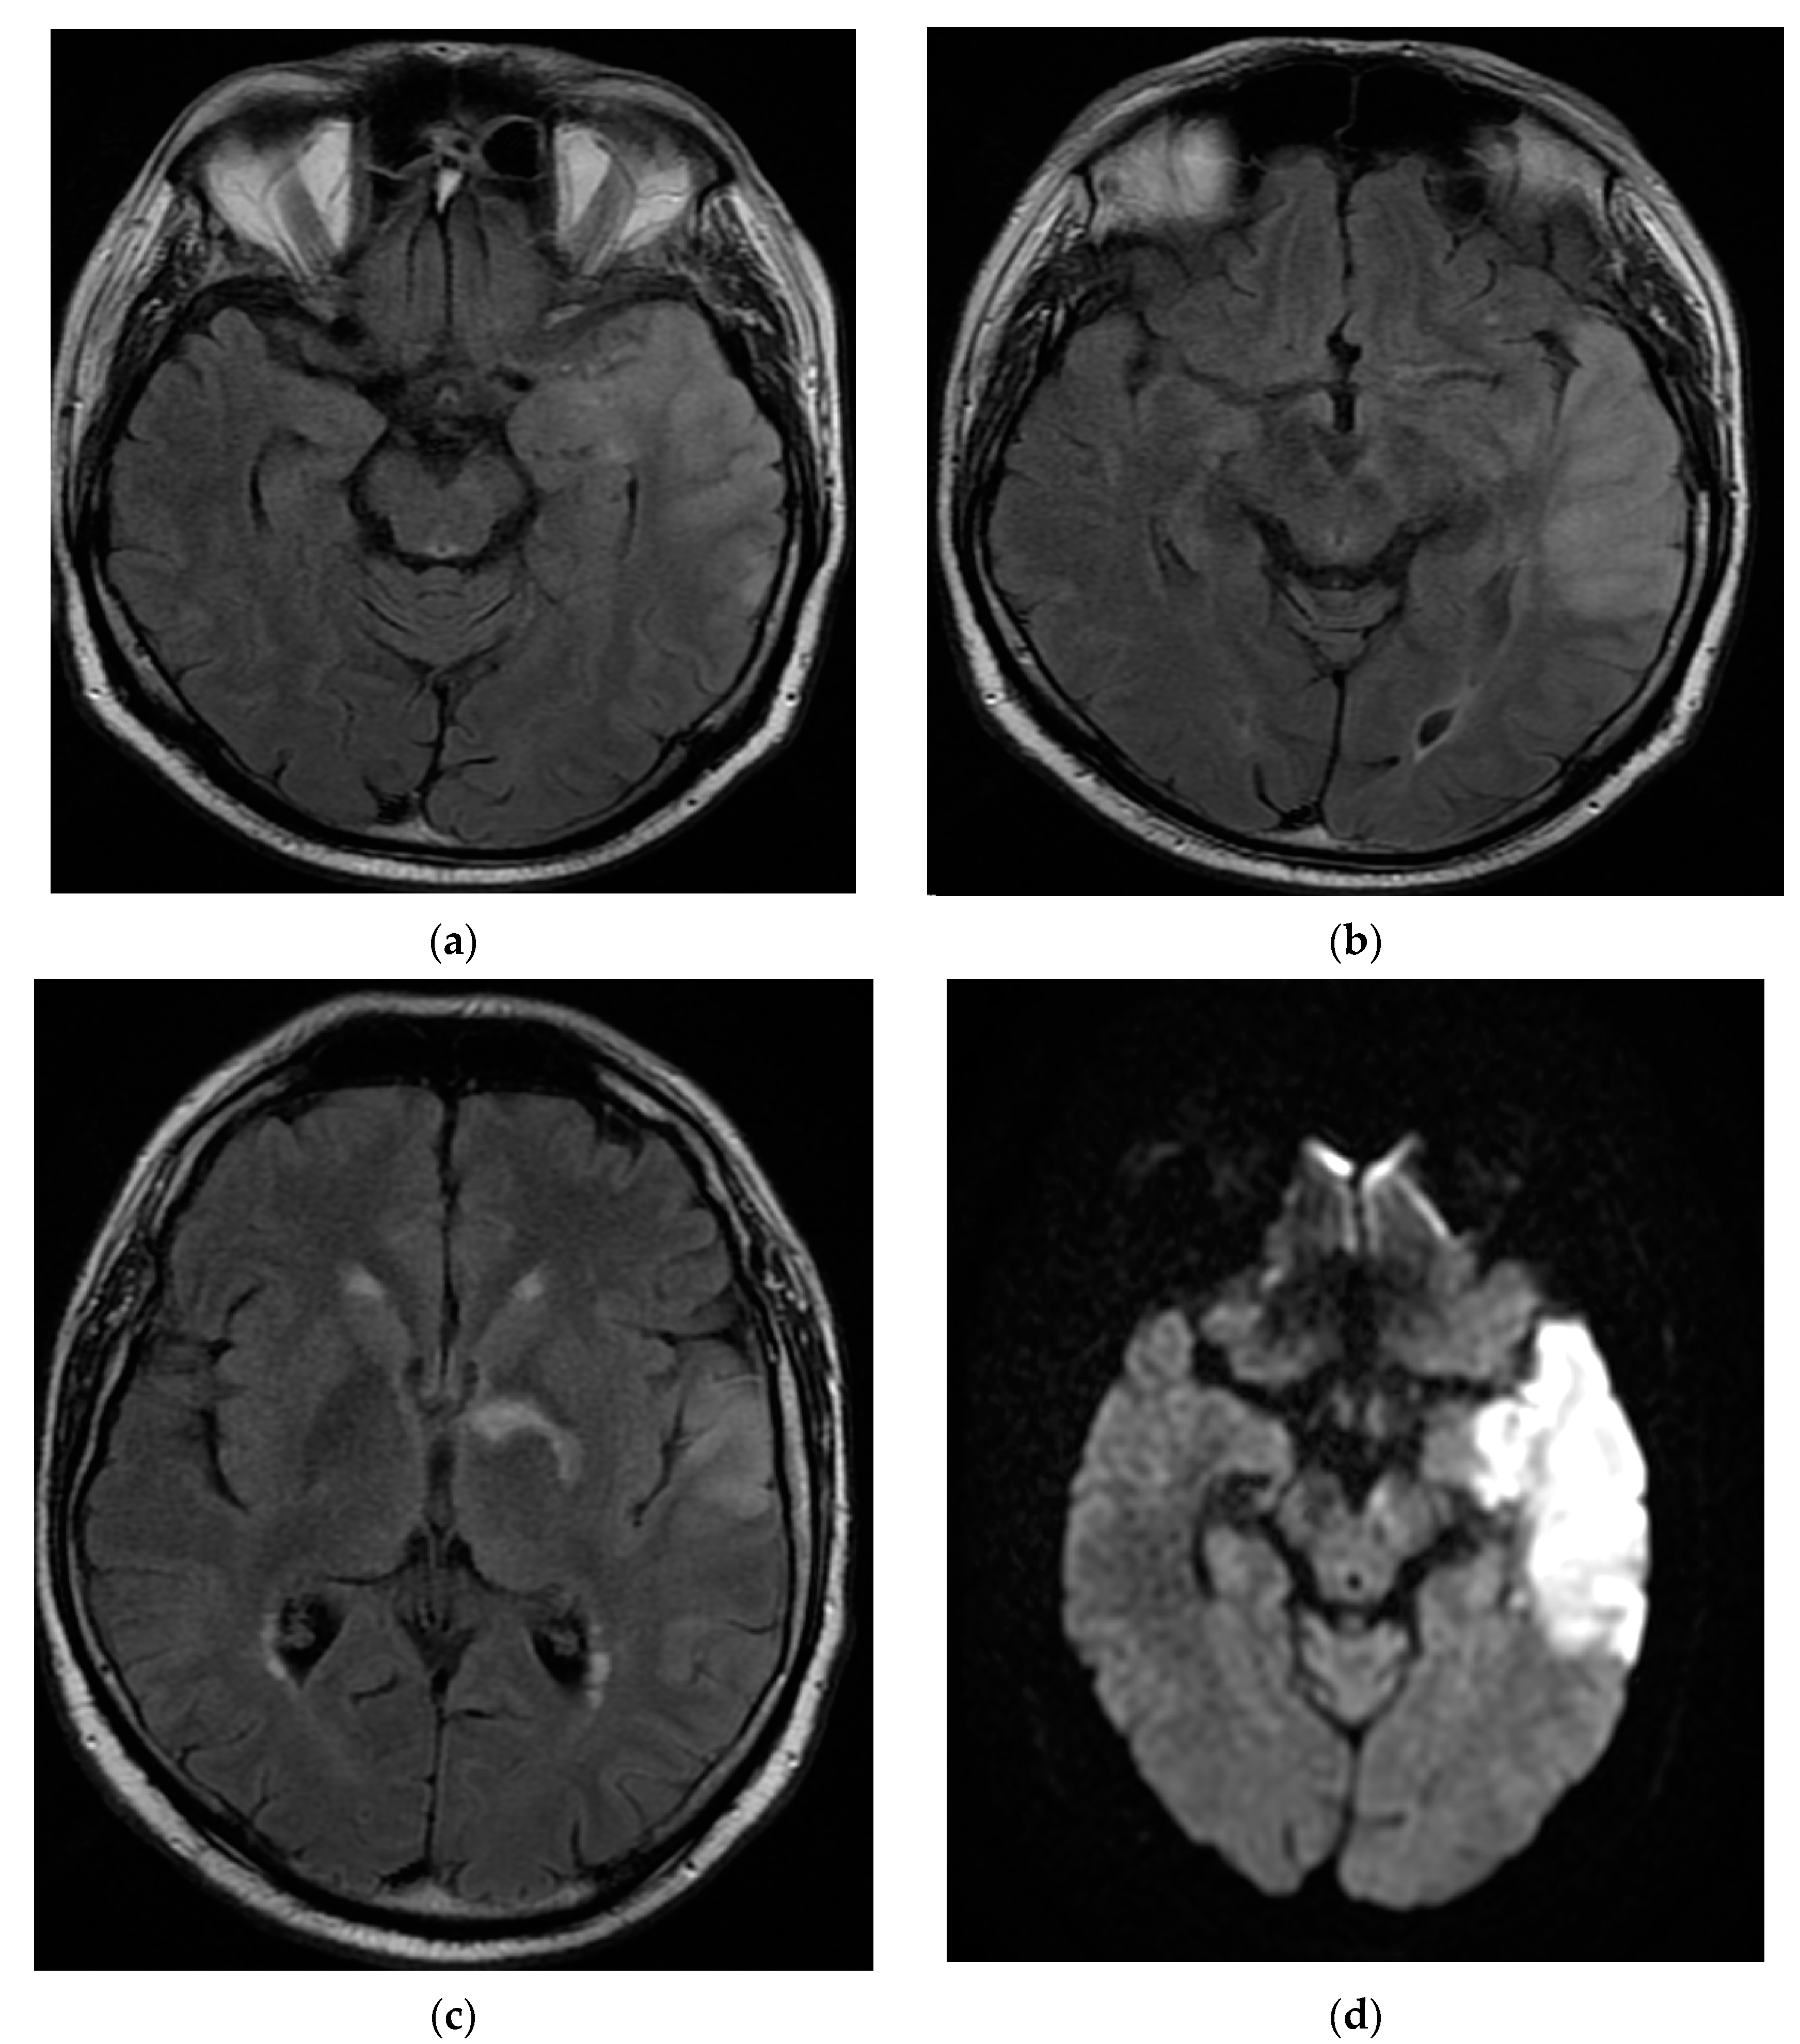

The patient continued to have worsening encephalopathy, and, after seven days, he presented with a depressed level of consciousness and extreme agitation. A repeat MRI brain scan with and without contrast showed extension of the lesion in the left fronto-parieto-temporal lobes with hypersignal aspects on the T2, Flair, and DWI images. Small hemorrhagic lesions were also shown in the left temporal lobe (hyperintense on T2 images) and in the posterior limb of the internal capsule. A hyperdense aspect capturing the contrast of the left middle cerebral artery wall was highlighted. The appearance was suggestive of the infectious/autoimmune vasculitis. The fronto-parieto-temporal meninges showed contrast capture on the Flair images (Figure 3).

Figure 3. MRI T2 axial Flair (a) and axial DWI (b) images demonstrated extension of the lesion in the fronto-parieto-temporal left lobes. Coronal T1 FSE (c) and axial T1 FSE (d) with contrast showing a hyperdense aspect of the left middle cerebral artery wall, suggestive of infectious/autoimmune vasculitis.